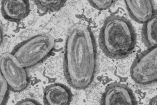

Esta enfermedad recibió su nombre cuando se descubró en monos de laboratorio en 1958